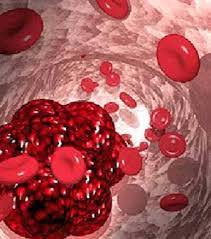

قیمت: 44٬000 تومان - دسته بندی فایل: تحقیق

قیمت: 44٬000 تومان - دسته بندی فایل: تحقیقپاورپوینت بیماری های خون در کودکان هموفیلی و لوسمی (ppt) 16 اسلاید

فروش ویژه پاورپوینت حرفه ای بیماری های خون در کودکان هموفیلی و لوسمی / تعداد اسلاید : 16 اسلاید